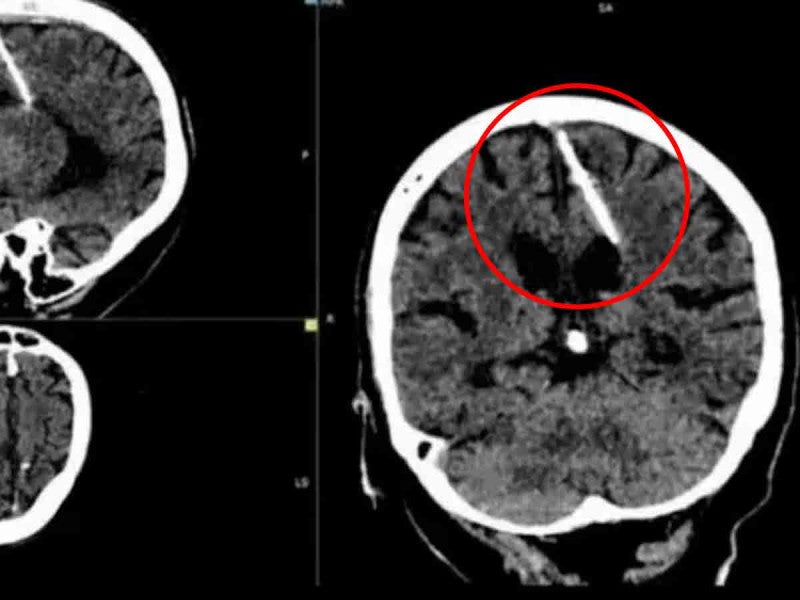

Cerebro de abuelita con aguja

Cerebro de abuelita con aguja Crédito: Redes

Lo que se suponía que sería un chequeo médico de rutina, se transformó en una sorprendente revelación en Rusia, cuando especialistas descubrieron una aguja de 3 centímetros de longitud en el cerebro de una mujer de 80 años.

Según el informe del Ministerio de Salud, los radiólogos identificaron el objeto durante una radiografía. Este incidente recuerda a un caso previo, donde a un soldado afgano se le encontró un explosivo en su cabeza hace varios años.

Aunque no se han proporcionado detalles precisos sobre el lugar y la fecha exacta del suceso, las autoridades sanitarias han confirmado que la aguja se encontraba en el lóbulo parietal izquierdo de esta mujer. Sorprendentemente, parece que la aguja estuvo en su cerebro desde su infancia, y nunca le causó molestias ni dolores de cabeza.

A pesar del sorprendente hallazgo, los médicos han decidido no extraer la aguja del cerebro de la mujer, ya que no representa un peligro inmediato para su salud.